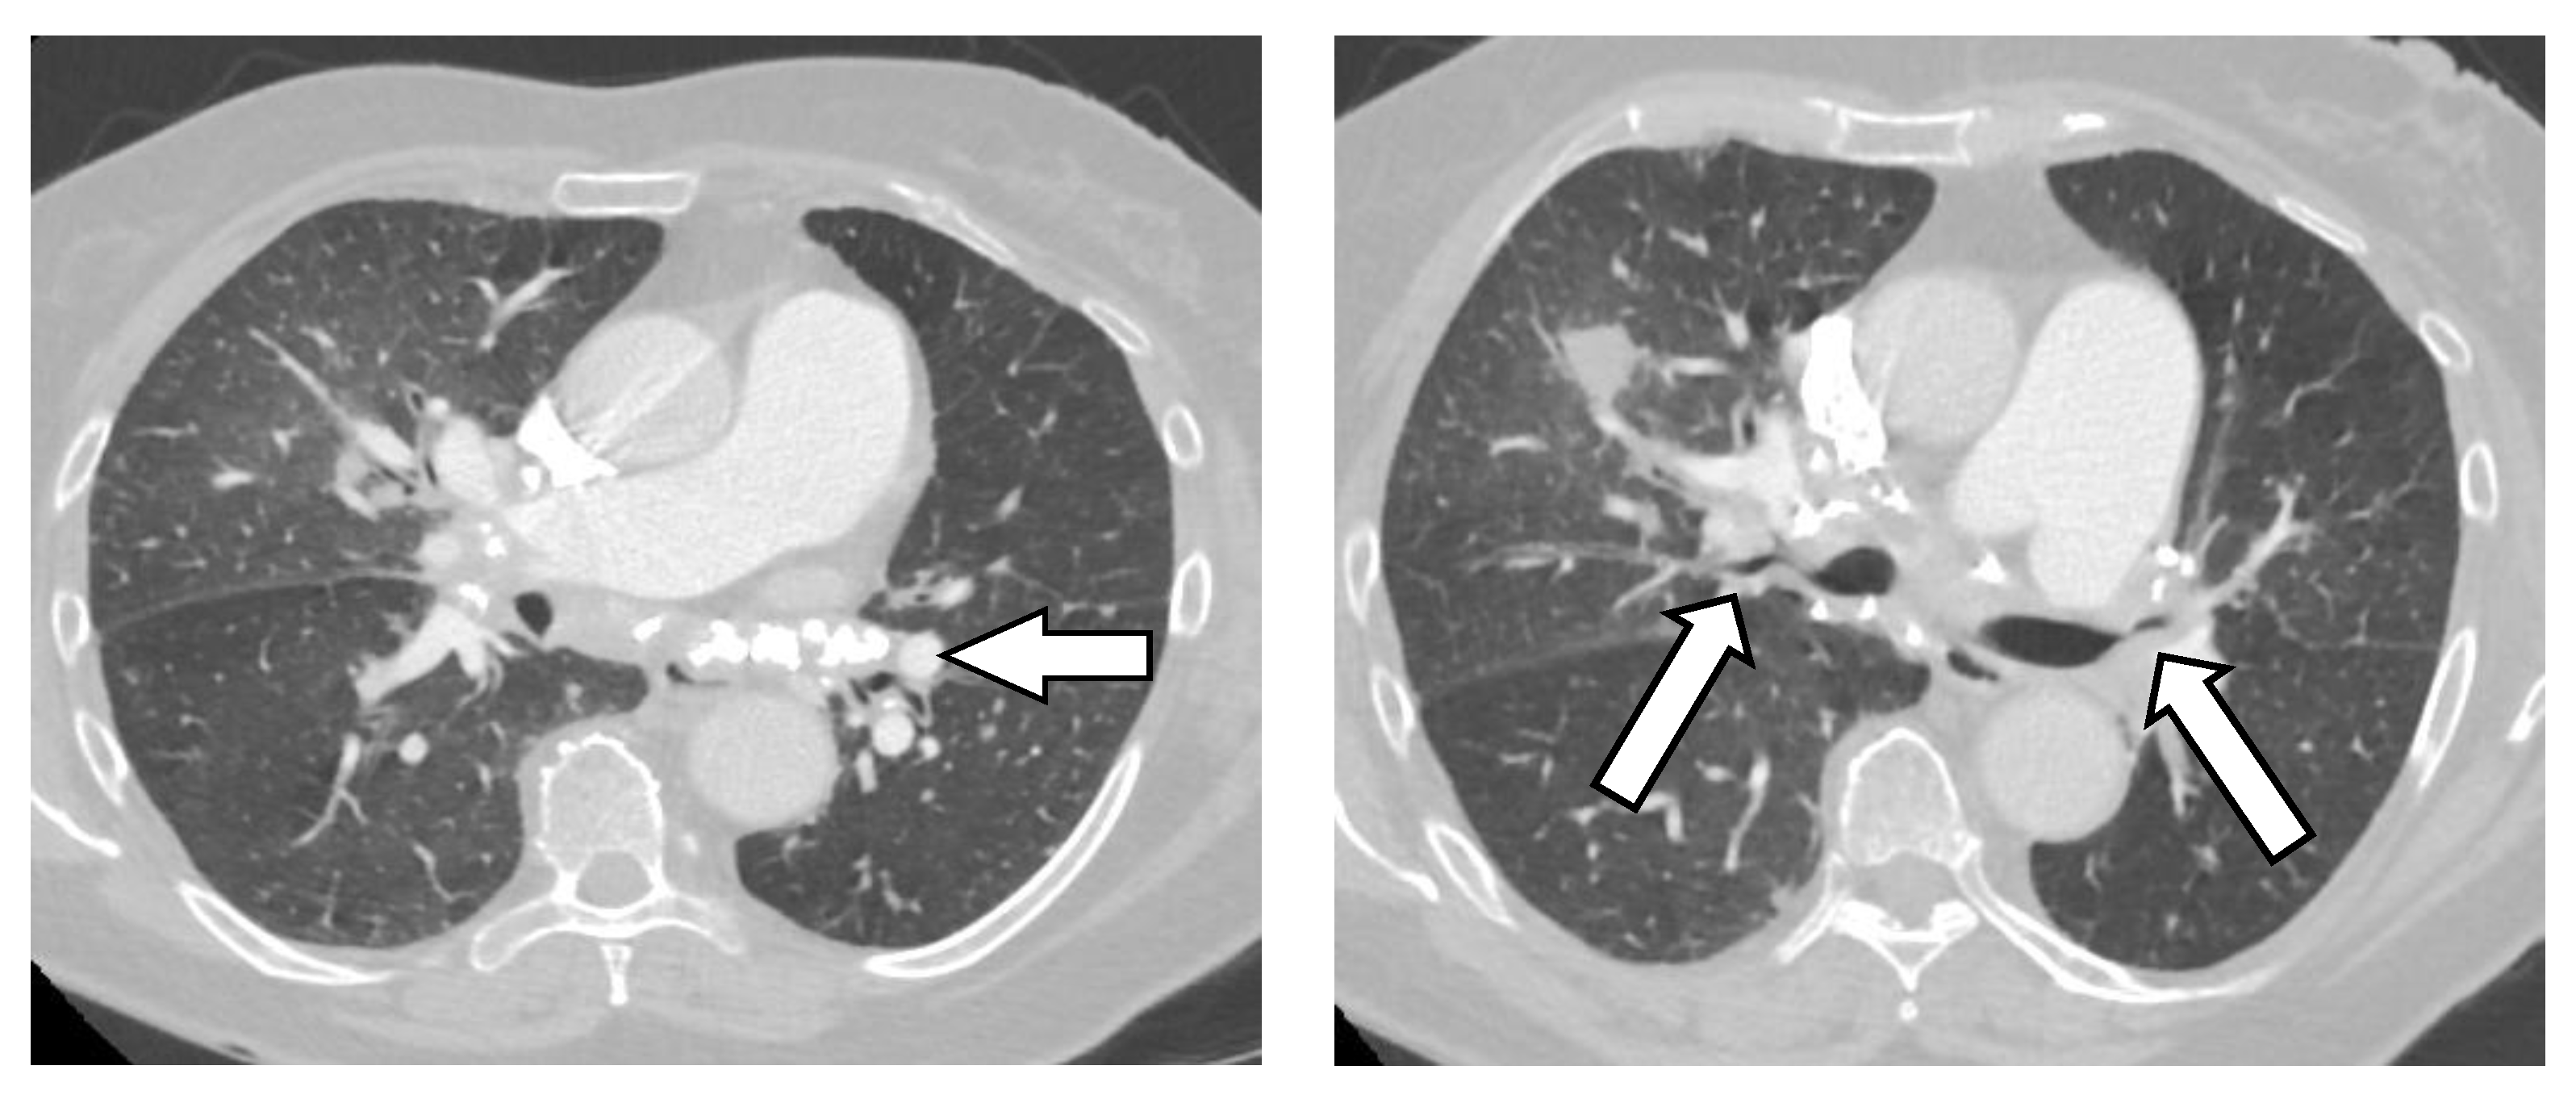

Chest X-rays can be deceptive as subcarinal masses may hide behind the cardiac silhouette. In contrast, chest CT reveals abnormal mediastinal proliferation with heavy calcification, usually localized at the lymph node sites (Figure 7). A FDG positron emission tomography (PET) scan shows intense FDG avidity in the mediastinal tissue.

Figure 7.

Fibrosing mediastinitis. (Left image) Arrows points at heavy calcification in the mediastinum. (Right image) both arrows point at severe stenosis of bronchial lumen.